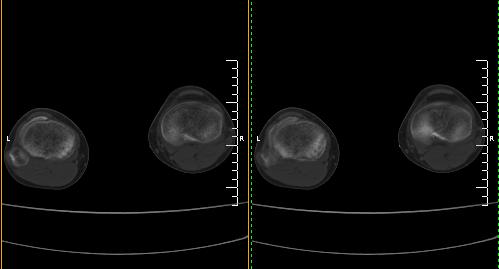

标题: CT19091:右胫骨近段骨性突出. [打印本页]

标题: CT19091:右胫骨近段骨性突出.

男,15岁,右胫骨近段软组织肿胀,下肢疼痛10左右.

支持考虑右胫骨内髁骨软骨瘤

支持考虑右胫骨内髁骨软骨瘤,不除外基底部骨折可能。

右胫骨近端内侧骨性突起,皮质连续,骨质结构正常,首先考虑胫骨骨软骨瘤,随访观察。